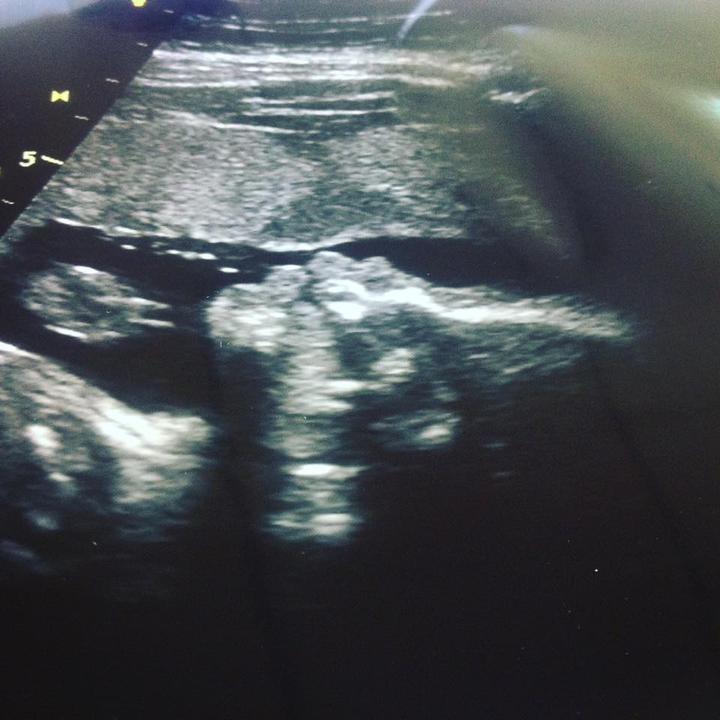

ČEKÁME :* ELIŠKU NA STO PROCENT !

16 týden :*

TAK VČERA SEM VIDĚLA TU NAŠÍ MALOU LÁSKU :*PĚKNĚ KOPALA UŽ SE TĚŠÍME ŠMUDLÍKU :* TVOJE MAMA A TÁTA :*